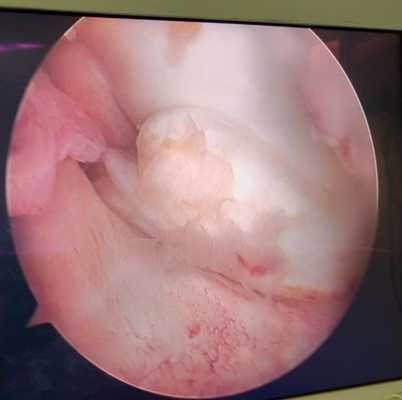

Дегенеративные изменения суставного хряща коленного сустава появляющиеся на фоне повреждения разорванным мениском.

Суставной хрящ - гладкая, упругая и прочная соединительная ткань покрывающая кости образующие сустав. Это позволяет костям свободно скользить друг относительно друга в суставном соединении. В случае травм, повышенного износа, некоторых метаболических расстройств хрящ может изнашиваться, вызывая боль и ограничение объёма движений. Артроскопия не лечит артрит или артроз, но может снизить болевой синдром и позволить частично восстановить хрящевое покрытие костей в суставе за счёт таких вмешательств как хондропластика, дебридмент и микрофрактуринг и ряд других.

Свободное внутрисуставное тело коленного сустава, состоящее из отслоенного участка хряща внутреннего мыщелка бедра на фоне его постоянной травматизации фрагментов разорванногомениска.

Свободное внутрисуставное тело коленного сустава после удаления, состоящее из отслоенного участка хряща внутреннего мыщелка бедра и причина отслойки - дегенеративно изменённый задний рог внутреннего мениска.